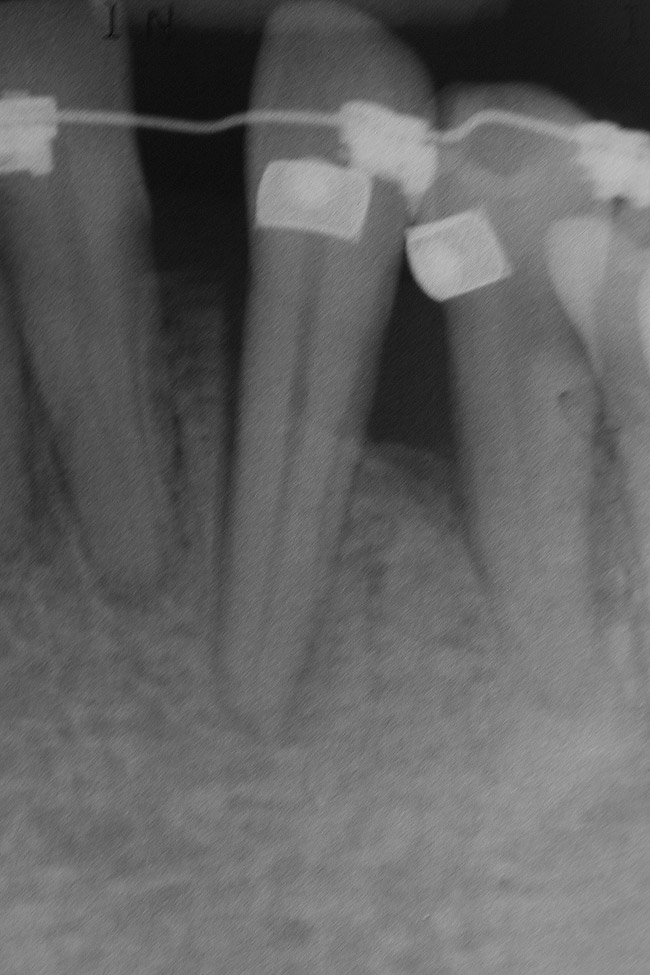

Figure 10  Radiograph of orthodontic distraction osteogenesis.

Figure 10

Figure 11  Radiograph showing developed implant site of tooth No. 23.

Figure 11